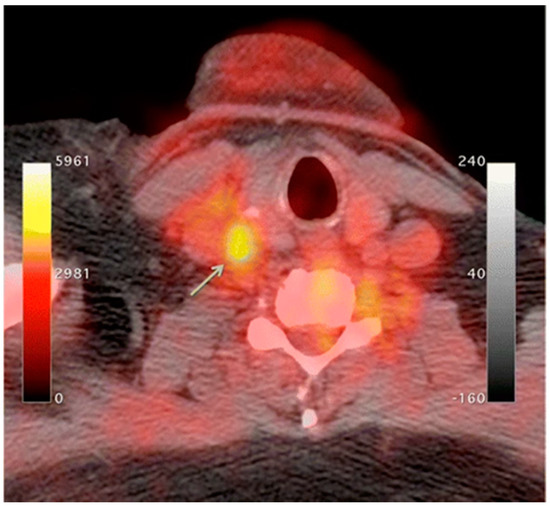

An increase in macrophage activity, reflective of inflammation, has been linked to a higher risk of plaque rupture; therefore, molecular imaging of macrophage activity in the arteries can help identify areas where plaque may be building [13][14][15]. 18F-Flourodeoxyglucose (FDG) PET imaging is commonly used to image the inflammatory component of atherosclerosis [16][17][18][19]. 18F-FDG is a radiolabeled glucose molecule, which is internalized by cells through the same mechanism in which glucose is metabolized. Both 18F-FDG and glucose are phosphorylated by hexokinase, where 18F-FDG becomes 18F-FDG-6-phosphate and glucose become glucose-6-phosphate. 18F-FDG-6-phosphate cannot be further metabolized by glucose-6-phosphate isomerase; therefore, it remains inside the cell for PET imaging [20]. In atherosclerosis, the accumulation of macrophages at locations of active plaque buildup requires a large amount of glucose, thus causing the upregulation of glucose transporters on the surface of these macrophages. Therefore, increased 18F-FDG uptake will be seen at locations of increased macrophage density, which is reflective of inflammation and active plaque buildup (Figure 1) [13][21]. It is unknown what the influence of 18F-FDG uptake from other cells, such as, neutrophils, endothelial cells, and lymphocytes, has on the observed signal [8][15]. Once the plaque cells have calcified, 18F-FDG uptake will subside substantially, making this type of PET imaging ineffective. PET imaging of atherosclerosis using 18F-FDG requires a circulation time of 2–3 h to allow for accumulation in the arterial wall and the decay or excretion of background levels of 18F-FDG [15]. 18F-FDG PET imaging in oncology typically needs 1 h of circulation time before imaging can begin.

PET imaging is currently the only clinically approved molecular imaging approach for GI inflammation [95][96]. Specifically, 18F-FDG PET is used to measure the extent and magnitude of GI inflammation, indicating areas of low or high inflammation based on metabolic differences throughout the GI tract. The high metabolic need of inflamed tissue alongside the increased presence and activity of immune cells, such as leukocytes, results in increased glucose metabolism at sites of inflammation [126]. Differences in 18F-FDG consumption highlight areas of increased inflammation while contrasting against normal healthy tissue. PET alone offers limited spatial resolution despite its potential for high contrast imaging. Additionally, the uptake of 18F-FDG occurs in off-target sites, resulting in high background signal. As such, PET is frequently paired with either CT or MRI imaging to better monitor disease status and accurately assess disease location, as shown in (Figure 5) [127][128][129].

Figure 5. (A) 18F-FDG PET image of human patient with Crohn’s disease. (B) T1-weighted magnetic resonance imaging (MRI) image of the same patient. (C) Merged PET/MRI. White arrows indicate locations of acute inflammation while red arrows highlight damage resulting from earlier disease action. The asterisk (*) shows a site of proliferation of fibrofatty compounds in the mesentery. SUVmax of 18F-FDG 5.6–9.2 vs. SUVmax of background bowel 1.5–2.8 [128].